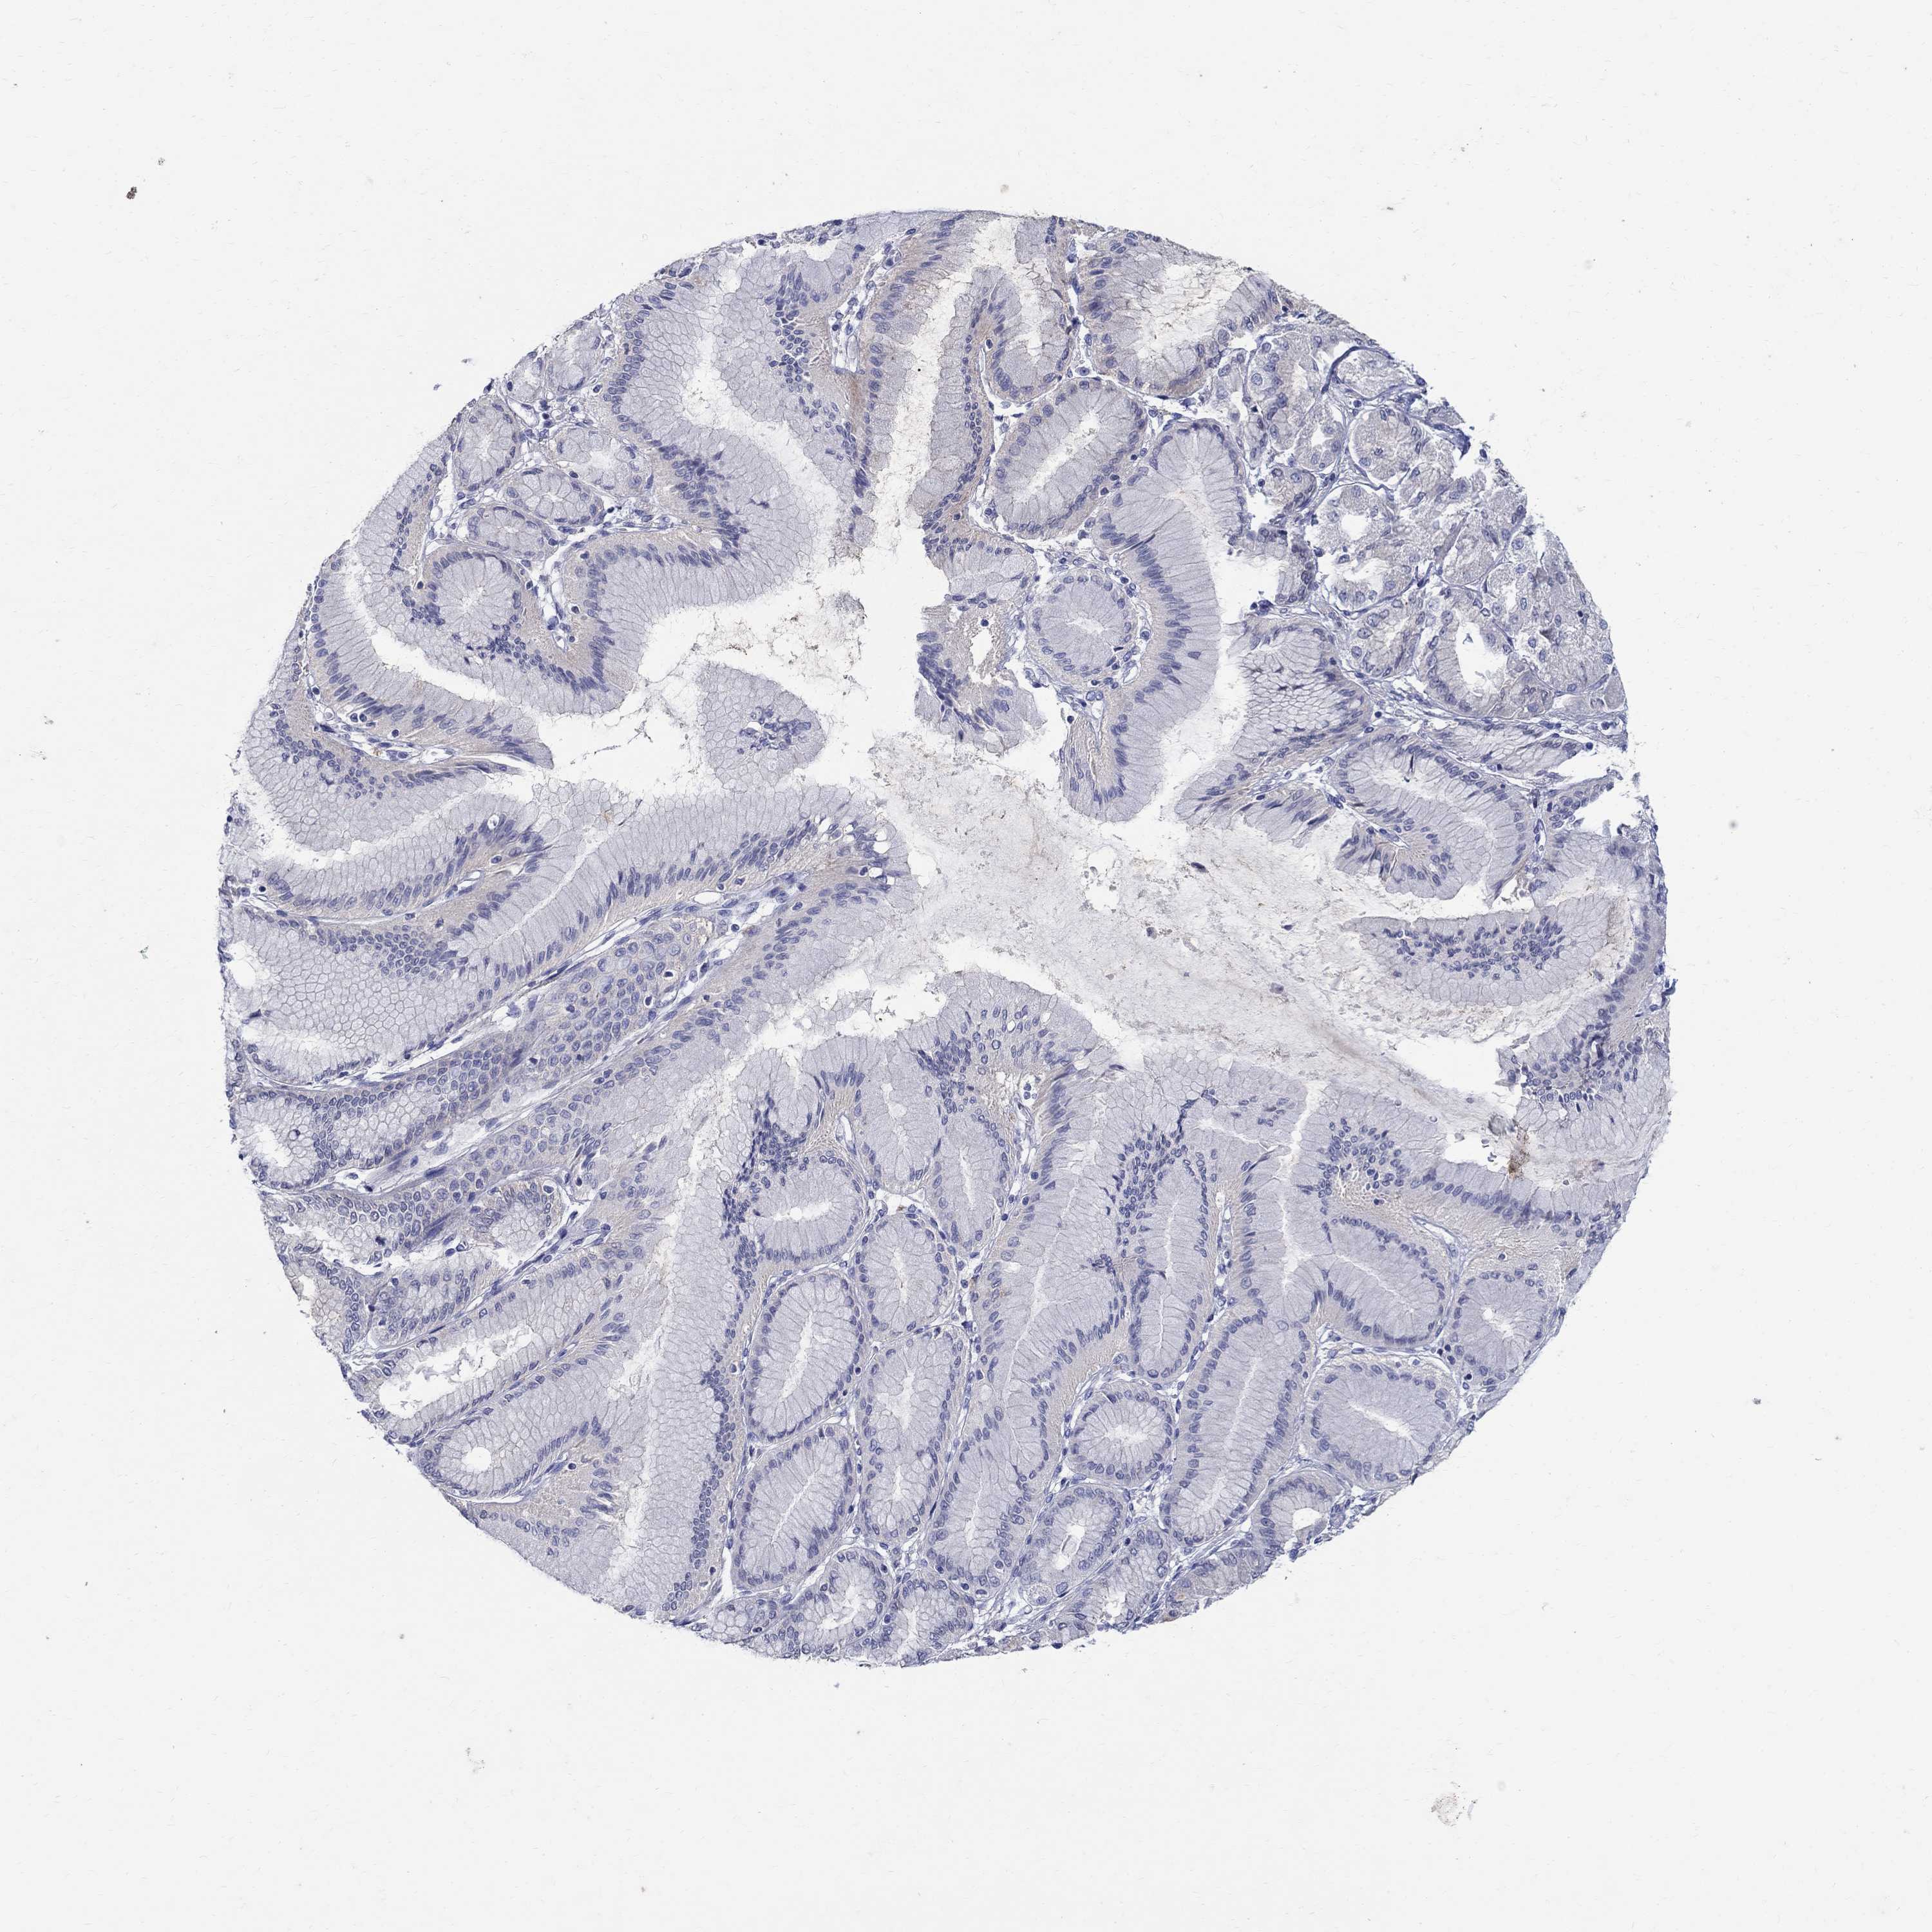

STOMACH CANCER - Protein expressioni

A mouse-over function shows sample information and annotation data. Click on an image to view it in a full screen mode. Samples can be filtered based on level of antibody staining by selecting one or several of the following categories: high, medium, low and not detected. The assay and annotation is described here.

Note that samples used for immunohistochemistry by the Human Protein Atlas do not correspond to samples in the TCGA dataset.

Antibody stainingi

Antibody staining in the annotated cell types in the current human tissue is reported as not detected, low, medium, or high, based on conventional immunohistochemistry profiling in selected tissues. This score is based on the combination of the staining intensity and fraction of stained cells.

Each image is clickable and will lead to virtual microscopy that enables deeper exploration of all samples and also displays staining intensity scores, fraction scores and subcellular localization as well as patient and tissue information for each sample.

Antibody HPA045725

Antibody CAB079745

Adenocarcinoma, NOS

Adenocarcinoma, High grade